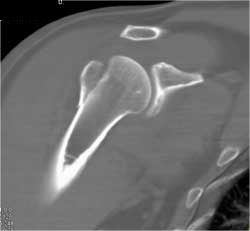

Humerus Fracture